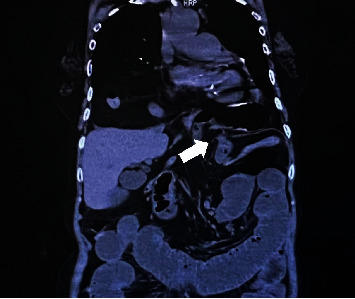

IV 型食管裂孔疝的特点是胃和相关器官(如脾脏、大肠、小肠和胰腺)通过食管裂孔疝出。这是一种相对罕见的食管裂孔疝,有时因胃嵌顿、胃内翻和绞窄而需要进行急诊手术。其中,小肠梗阻极为罕见,需要手术治疗。我们报告了一例因回肠嵌顿食管裂孔导致小肠梗阻而入院的 83 岁妇女的病例,该患者接受了紧急腹腔镜手术。

Type IV hiatal hernia of the esophagus is characterized by herniation of the stomach and associated organs, such as the spleen, large and small bowel, and pancreas, through the esophageal hiatus. It is a relatively rare form of hiatal hernia that sometimes requires emergency surgery due to gastric incarceration, volvulus, and strangulation. Of these, small bowel obstruction is extremely rare and requires surgery. We report the case of an 83-year-old woman who was admitted to the hospital for small bowel obstruction caused by an ileum that had incarcerated the esophageal hiatus; emergency laparoscopic surgery was performed.